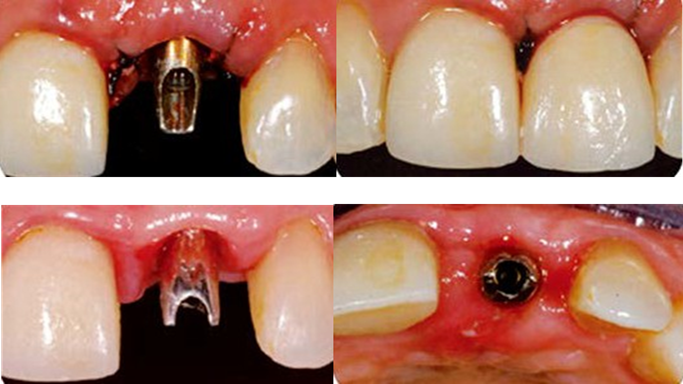

“Immediate loading of single AnyRidge implants

is a highly successful treatment modality. ”

Clinical case: Immediate post-extraction insertion of implant & immediate loading

- Courtesy of Prof. Giuseppe Luongo, Italy -

AnyRidge, immediate loading, single implant, multicenter study, maxillary anterior, Prof. Giuseppe Luongo, single replacement

AnyRidge implant system

Immediate functional loading of single implants: a multicenter study with 4 years of follow-up

/J Dent Res Dent Clin Dent Prospect 2018; 12(1):26-37 | doi: 10.15171/joddd.2018.005

https://www.ncbi.nlm.nih.gov/pubmed/29732018